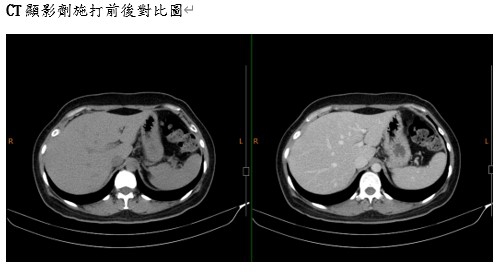

√含碘成分,多數使用在電腦斷層攝影,血管透視攝影,輸尿管透視攝影它們限制X光穿透。於是在X光或電腦斷層影像上有顯影的血管、器官,或其他身體 組織看起來會不一樣。被顯影劑附著的血管或組織就會看起來白白亮亮的。